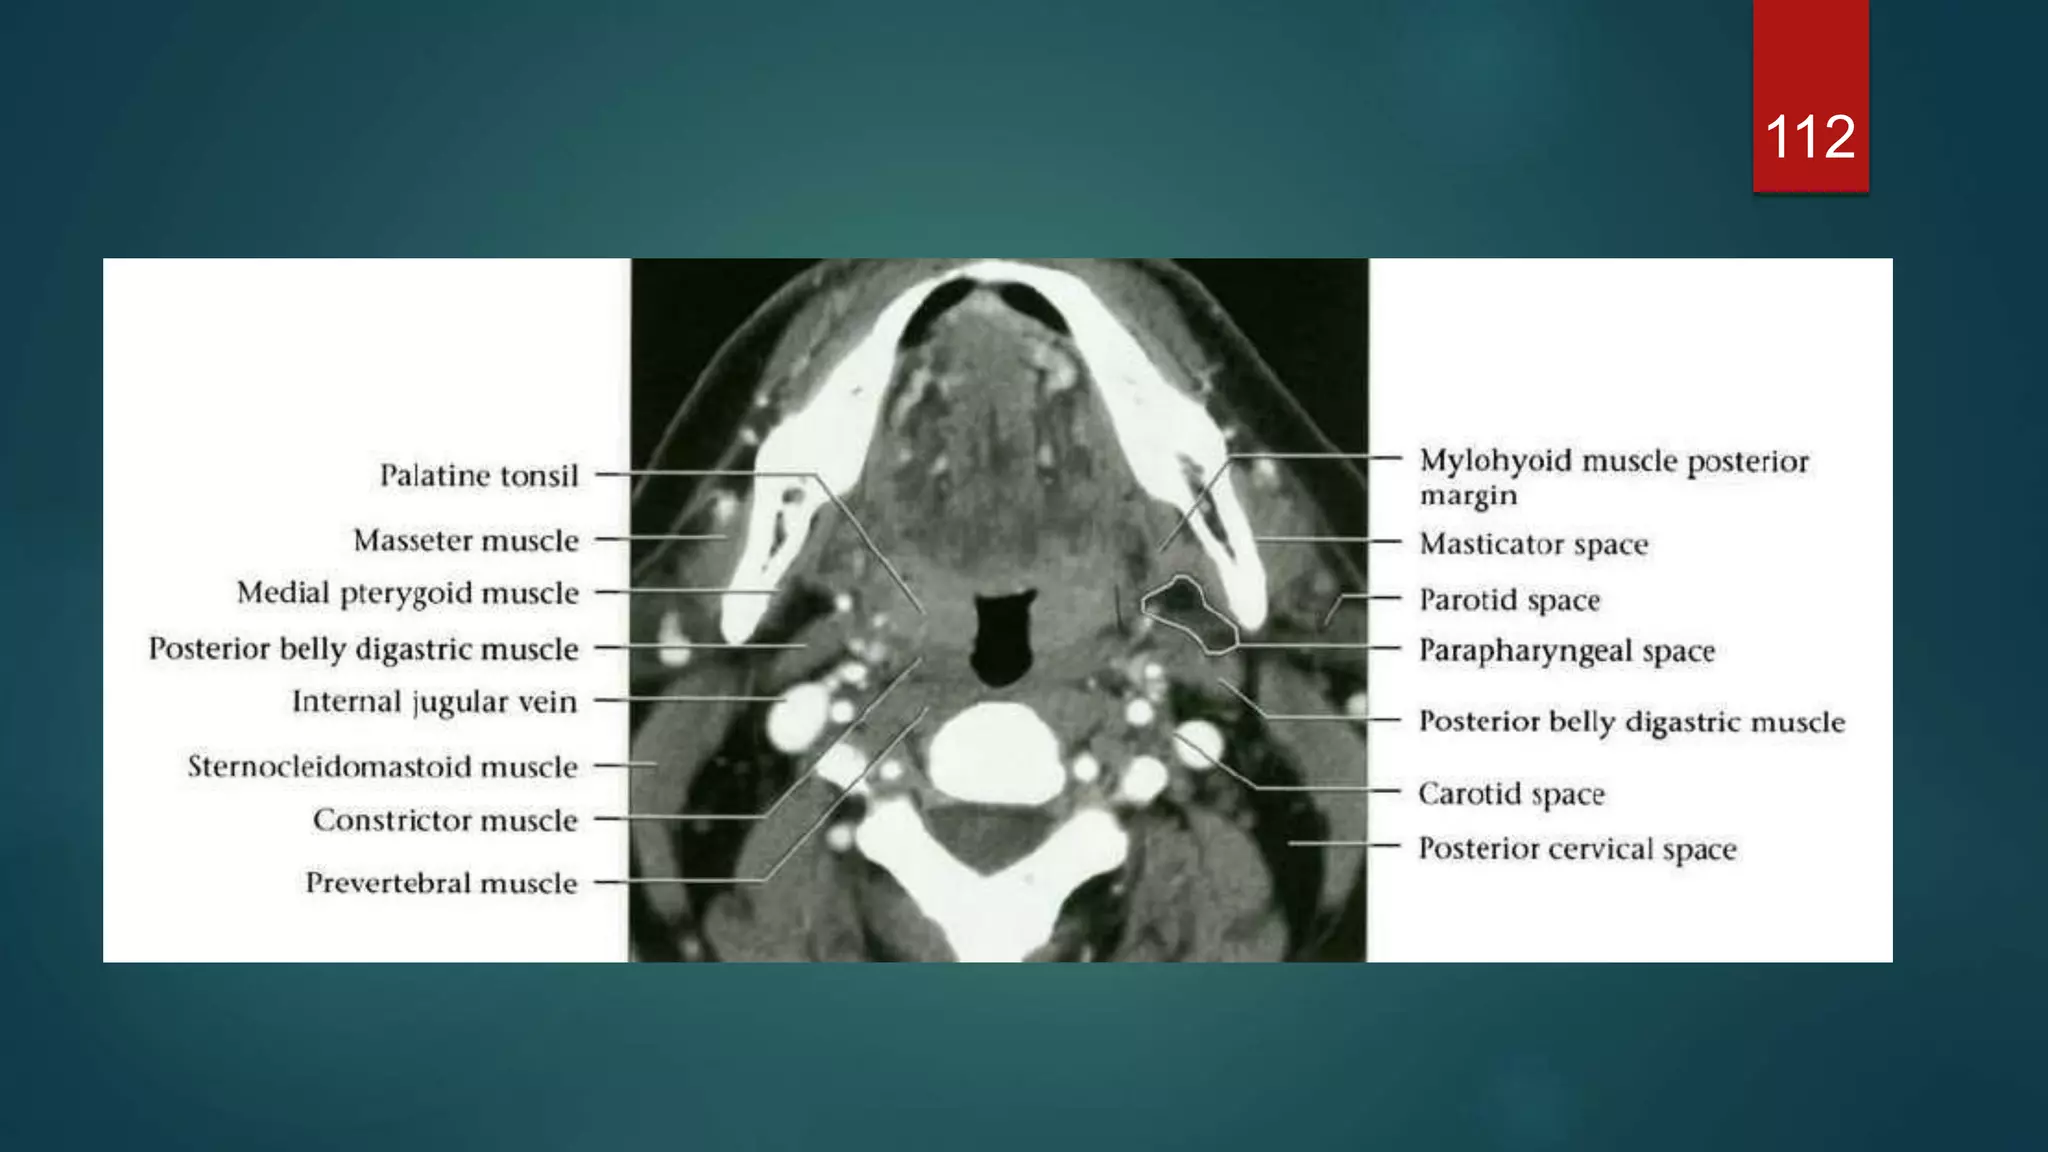

CAROTID SPACE

 Paired tubular structure traversing SHN

and IHN

 Skull base to superior mediastinum

 Lateral to RPS

 Enveloped by carotid sheath : all 3

layers of DCf

 Contents : SHN – ICA IJV , CN9-12,

:IHN - CCA, IJV , CN10 trunk (

vagus)

 The bifurcation of the common carotid

usually occurs at the boundary of the

suprahyoid and infrahyoid spaces

112